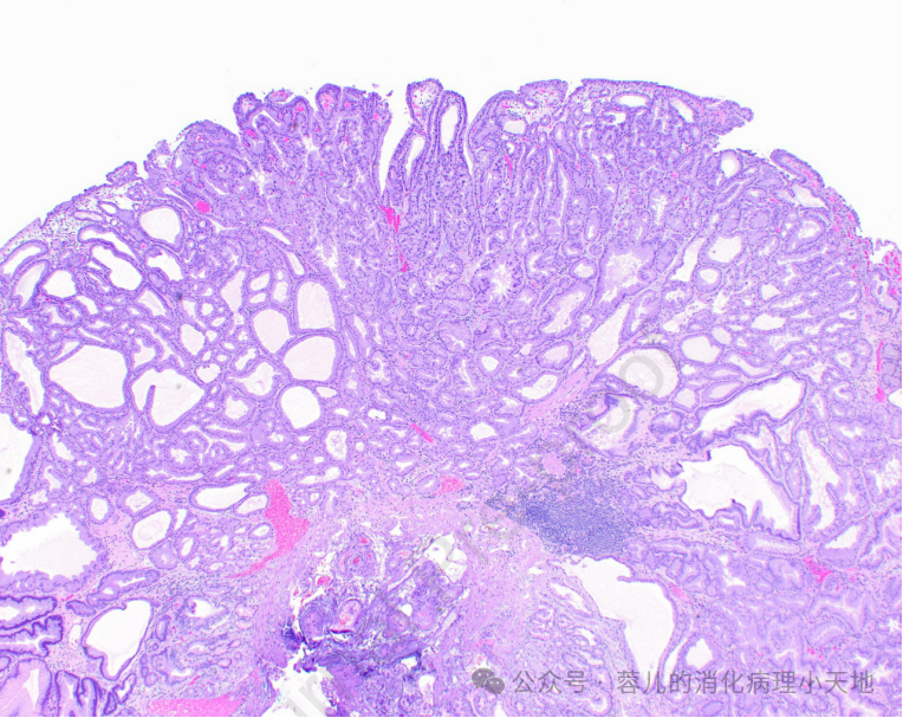

形成病变的胃异型增生(肠型腺瘤)具有肠型表型,表现为密集的腺体,由深染的肿瘤细胞排列而成,累及胃窦黏膜

病变细胞缺乏粘蛋白,并含有铅笔状假复层核,这些核保持与基底膜的关系

组织学特征:密集排列的腺体,由深染的肿瘤细胞构成,细胞缺乏粘蛋白,含铅笔状假复层核,且核与基底膜保持关系